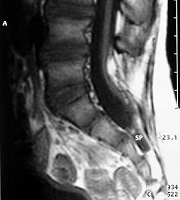

La espina bífida abierta prácticamente ya no se ve, y son el mielomeningocele, el meningocele y el mielocele. El tratamiento preventivo antes del embarazo (3 meses) y durante el embarazo (3 primeros meses) ha hecho que desaparezcan: de cualquier forma cuando ocurre, en nuestra opinión el tratamiento es la intervención quirúrgica.

La espina bífida oculta está formada por las malformaciones como los lipomas, senos dérmicos, diastematomielia, etc. que anclan la médula. Se operan con técnicas microquirúrgicas antes del año de vida.